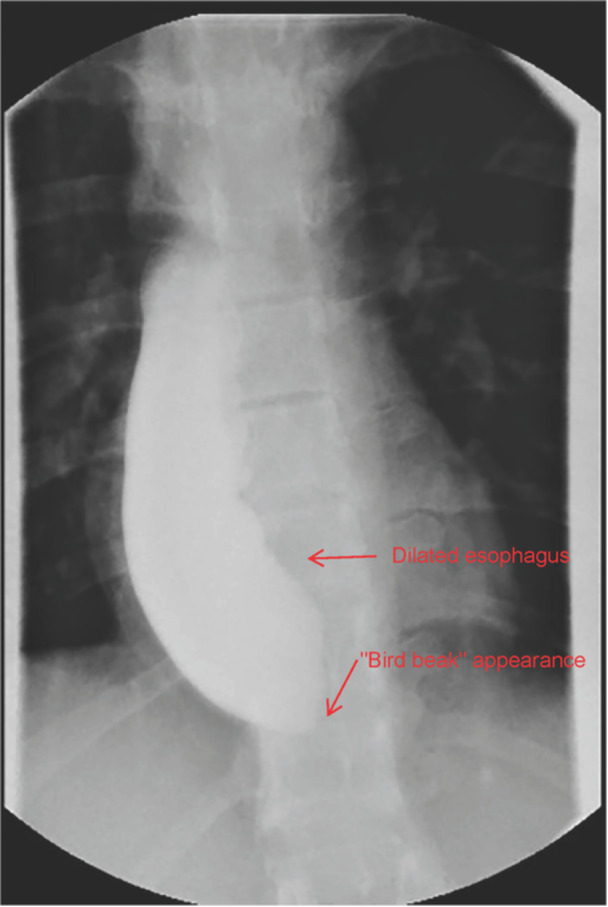

We report the case of a 19-year-old White male diagnosed with familial adenomatous polyposis (FAP), Gardner's syndrome (GS) phenotype, status post total colectomy, who developed progressive dysphagia and weight loss. He was diagnosed with achalasia based on imaging and esophageal manometry. The patient underwent a Heller myotomy with the resolution of symptoms. To date, no previous literature has reported on concurrent FAP or GS and achalasia. Although FAP and achalasia are both rare conditions with no previously known concurrent occurrence, association, or described syndrome, it is important to be vigilant of this new case report finding. One must also consider the increased risk of malignancy in patients with achalasia in addition to the significant risk of malignancy in patients with FAP/GS.